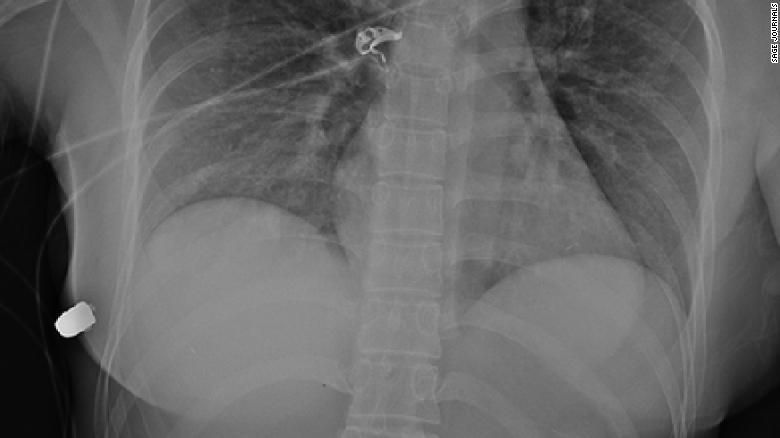

Folosind radiografii traumatice, medicii au reușit să detecteze glonțul în peretele toracic lateral drept, o coastă fracturată și bule de aer în sânul stâng. Medicii au cloncluzionat că glonțul ”a călătorit” de la sânul stâng la peretele toracic drept.

Medicii au găsit un obiect dur, asemănător glonțului în peretele toracic anterior inferior al femeii sub pieptul drept.

„Intrarea plăgii glonțului a fost pe sânul stâng, dar fractura coastei a fost pe partea dreaptă. Glonțul a intrat mai întâi în pielea din partea stângă, apoi a ricoșat peste stern în sânul drept și i-a rupt coasta în partea dreaptă.”, a explicat medicul.

„Implantul a provocat schimbarea traiectului glonțului”, a spus el.